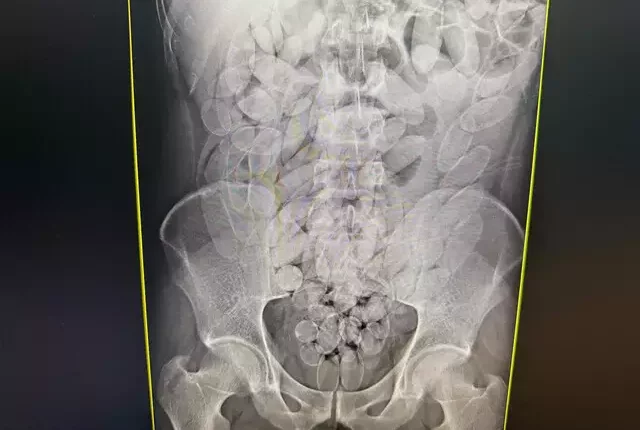

Os raios X confirmaram que os oito haviam engolido cápsulas de pasta base de cocaína. O material foi retirado de forma segura por equipe médica, totalizando 645 cápsulas. Após o procedimento, todos foram encaminhados à PF (Polícia Federal), onde permanecem à disposição da Justiça.